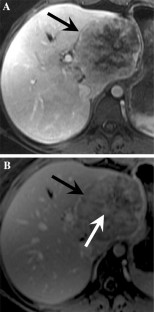

Fig. 1